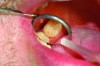

Accurate impressions of the upper and lower dentition are required for custom fabrication of a MAD. Because some appliances extend beyond the teeth, it is recommended that the impression capture at least 3-4 mm of soft tissue surrounding the teeth. The lower impression must capture the distal surfaces of the most distal teeth on both sides of the arch. The MAD must be fabricated to extend to include these surfaces; otherwise, diastemas may form with the adjacent mandibular teeth (Figure 2 through Figure 4).

Fig 2. Inadequate posterior extension of a MAD. The posterior extent of the MAD failed to capture the distal surfaces of the mandibular second molars. All third molars were absent.

Fig 3. Eight months later, diastemas had developed between the mandibular second and first molars.

Fig 2. Inadequate posterior extension of a MAD. The posterior extent of the MAD failed to capture the distal surfaces of the mandibular second molars. All third molars are absent.

Fig 3. Eight months later, diastemas have developed between the mandibular second and first molars.

Figure 2

Figure 3